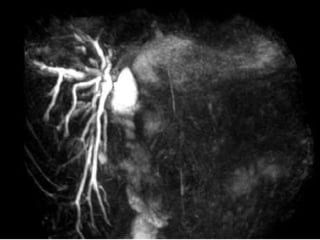

PATOGÊNESE  Isquemia Lesões complexas Strasberg E3-5, Bismuth>3 CT angio MRA Angiografia

PATOGÊNESE IsquemiaLesões complexas Strasberg E3-5, Bismuth>3 CT angio MRA Angiografia